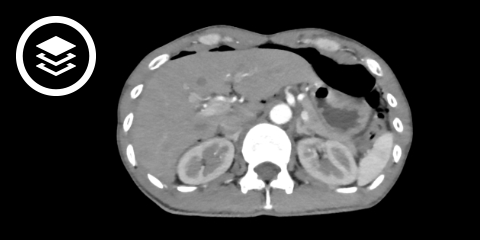

Peritonitis

Die Peritonitis ist eine Entzündung des Bauchfells (Peritoneum).